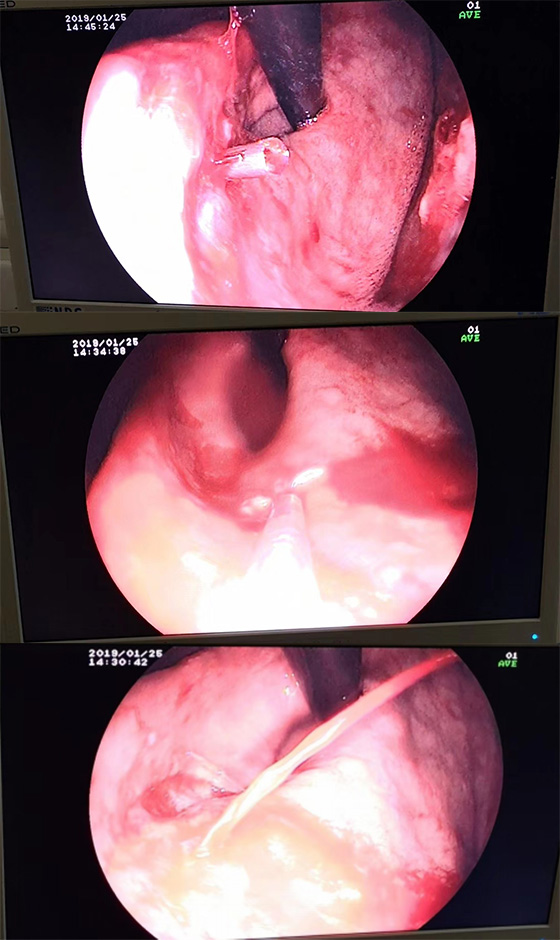

日前,一名60多岁的老人突发“一氧化碳中毒”,在我院神经内科住院治疗好转后,计划出院当天突发解黑便,经过消化内科会诊协助治疗后,患者1月25日再次突发呕血600ml,并出现失血性休克。在神经内科盛守权主任指导下,经郭城医生等医护人员的补液输血等治疗后,患者生命体征趋于平稳。在消化内科刘东升主任会诊后,建议进行床边胃镜检查,明确出血原因,必要时内镜下治疗。1月25日下午和患者家属充分沟通后,在总务科协助把内镜搬到患者床边,在刘东升主任指导下由吴斌主治医师进行急诊内镜检查。胃镜结果显示患者胃体上部大弯有一血管喷射样出血,属于罕见的杜氏病,应立刻内镜下治疗。在内镜室柯星梅主管护师和张晓苹主管护师的配合下,进行了“组织胶+钛夹”内镜下治疗,终于成功止住出血。后患者转入消化内科进一步治疗,已于年前康复出院。

杜氏病是消化内科急重症,起病急,出血量大,常导致失血性休克,可直接威胁患者的生命。而且该病病灶小、隐匿,且出血前多无先兆,病因罕见,很多经验不足的医生对这个病也认识较少,导致诊断困难。通常杜氏病所致上消化道出血的首选方案是内镜下治疗。对于早期出血患者,内镜下治疗能防止病情恶化,如处理得当能一次止血成功,创面较小的患者恢复快。因大部分内镜下操作无需麻醉,对合并心脑血管疾病的患者风险相对较小。